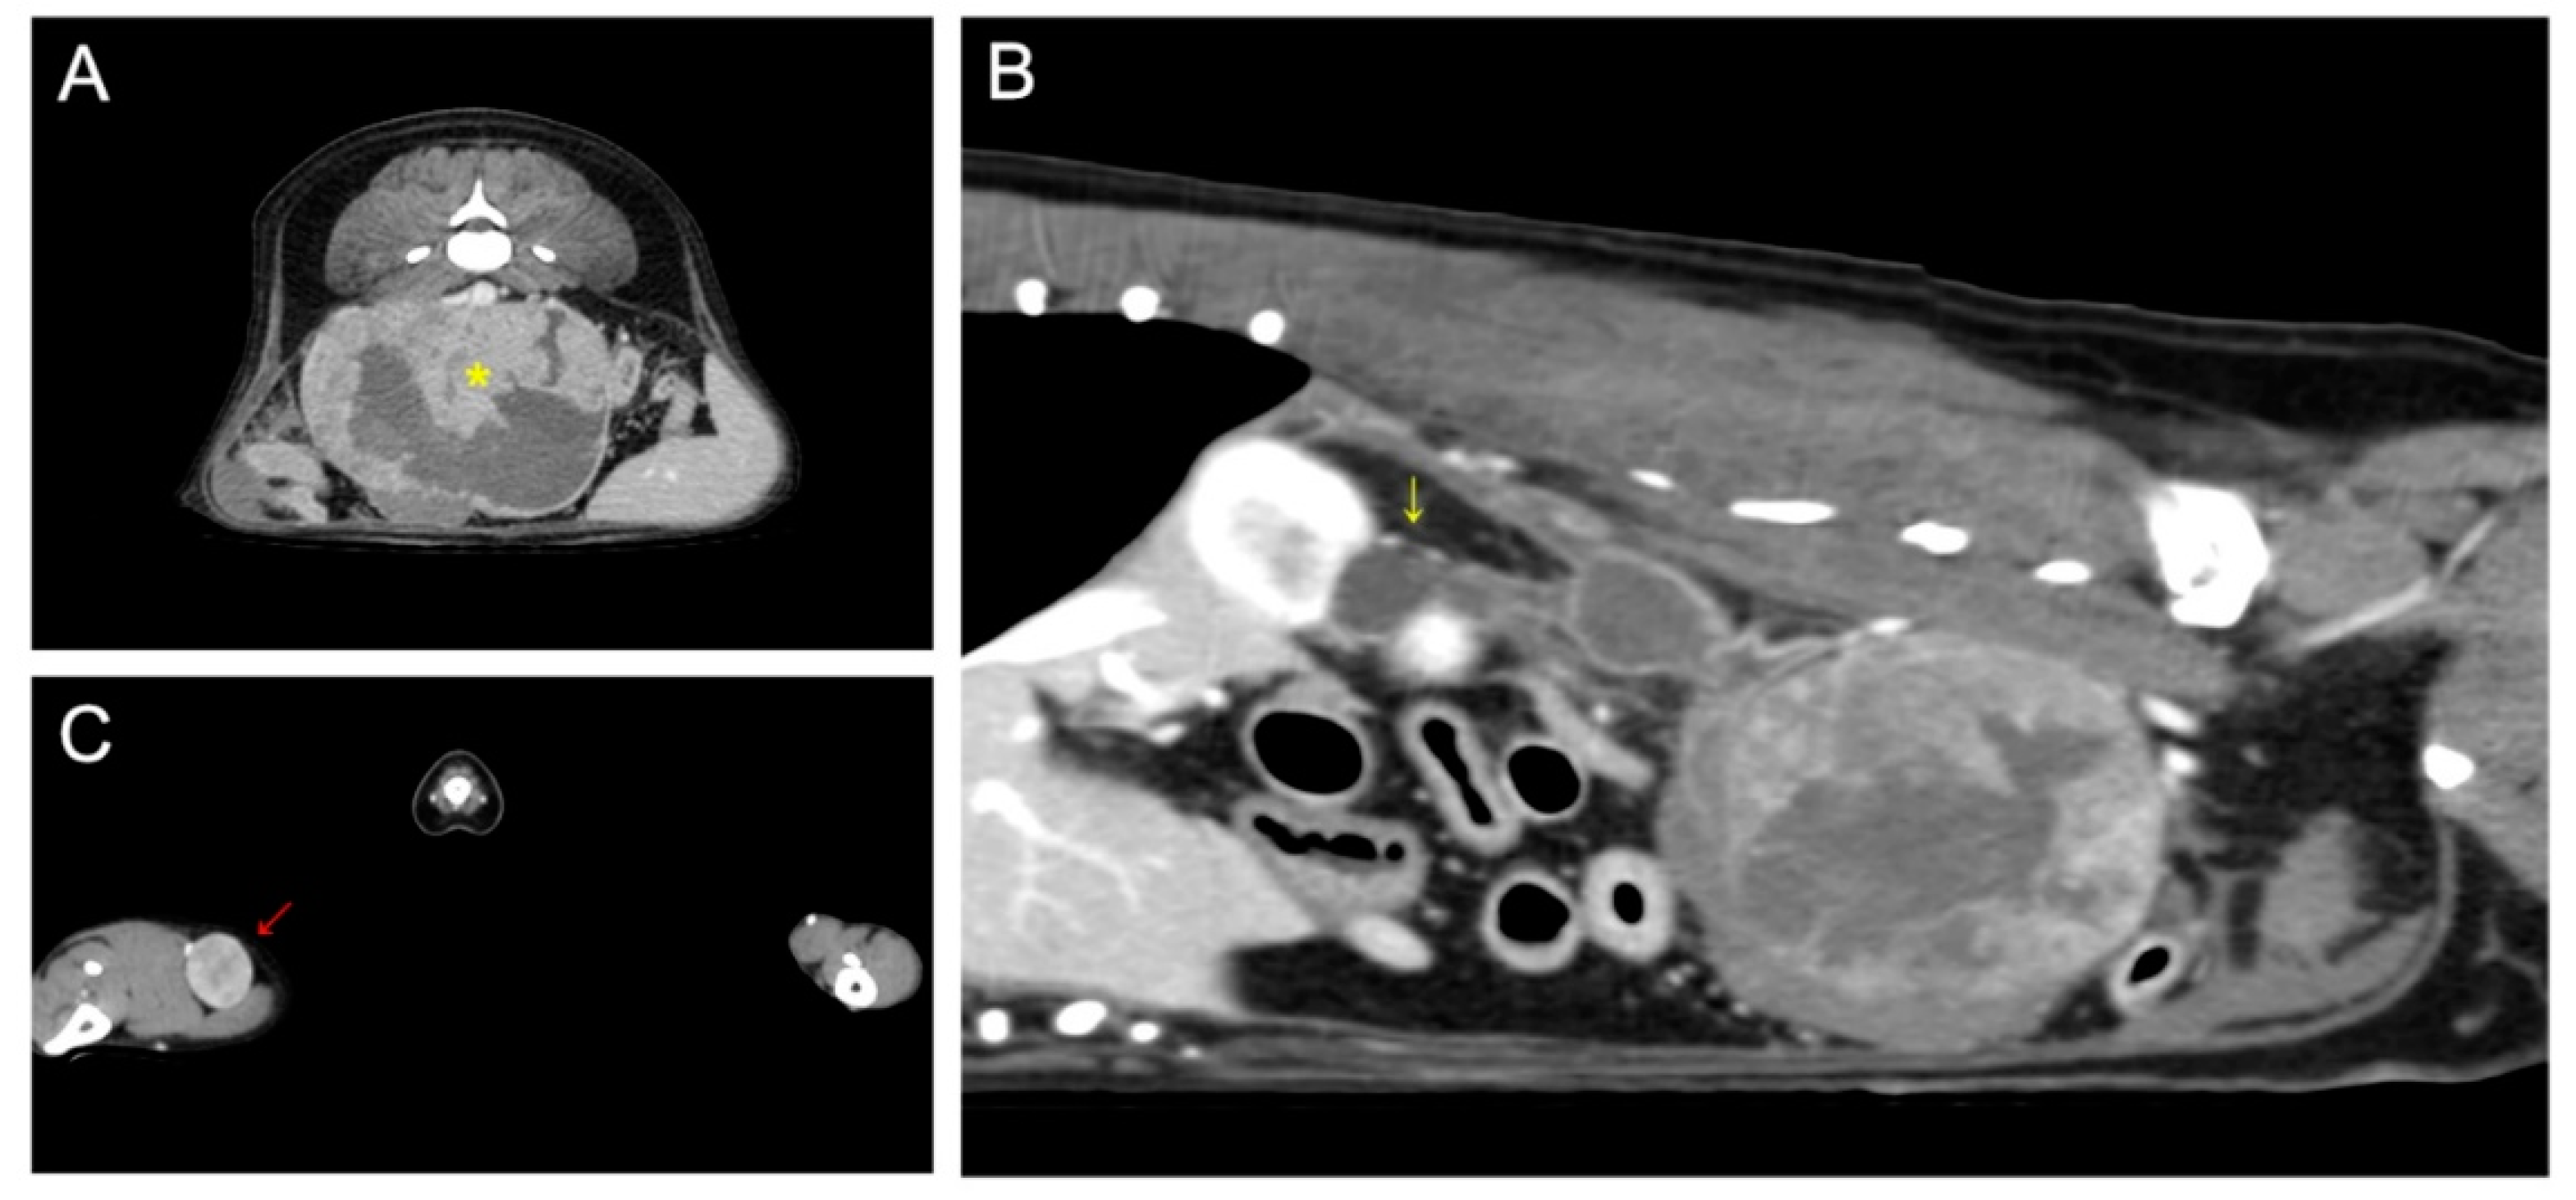

On computed tomography, a 93 × 72 × 65 mm abdominal mass with necrotic changes was closely adjacent to the caudal vena cava, abdominal aorta, right deep circumflex iliac artery, and external iliac artery (Figure 1). Severe hydroureteronephrosis was observed in the upper right urinary tract. A 22 × 19 mm right popliteal lymph node showed heterogeneous postcontrast enhancement, and the lymph node was suspected to be a metastatic lesion. Malignant glandular epithelium was confirmed on fine-needle aspiration of the right popliteal lymph node, but diagnostically valuable samples could not be obtained from the metatarsal skin mass.

Figure 1. Preoperative computed tomography: (A) retroperitoneal mass (yellow asterisk) suspected of being metastasis from the right metatarsal skin mass; (B) proximal hydroureteronephrosis (yellow arrow) caused by compression of the distal ureter by the retroperitoneal tumor; (C) enlarged right popliteal lymph node (red arrow).